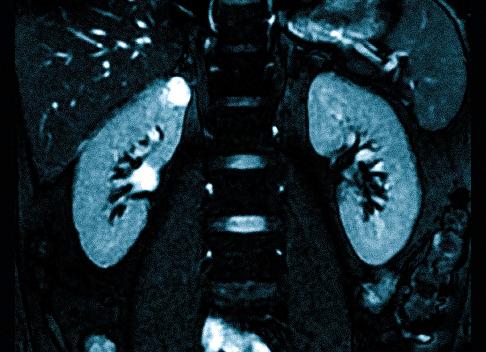

МРТ почек с контрастным веществом. МРТ почек без контраста

Магнитно-резонансная томография почек – уникальный метод исследования, который позволяет вычислить патологию органов даже на стадии ее формирования. Технология МРТ основана на воздействии магнитных полей, в результате чего после диагностики специалист может оценить 3d реконструкцию исследуемых органов на экране. Для более высокой точности результата показано МРТ почек с контрастированием. Методика МРТ почек без контрастов помогает точно выявить наличие или же отсутствие патологического нарушения. Однако введенный контрастный препарат способствует повышению информативности обследования и визуализации всех дополнительных данных о новообразовании. К тому же, способ контрастного МРТ почек рекомендуется к проведению с целью диагностики состояния почечных сосудов и вычисления мест их поражения. Но, несмотря на преимущества, контраст категорически противопоказан к применению для пациентов с почечной недостаточностью и другими заболеваниями, которые в медицине классифицируются как «тяжелые».

Использование метода магнитно-резонансной томографии предусматривает применение свойств магнитного поля и радиочастотных импульсов, с помощью которых удается получить максимально достоверные послойные снимки, которые покажут наличие заболевания и место его локализации. Благодаря МРТ можно получить такие данные:

- магнитно-резонансная томография показывает, какого размера орган, состояние сосудов и существуют ли изменения в структуре тканей;

- нормального ли строения почки, или есть патологии;

- есть ли новообразование и существуют ли предпосылки к его увеличению;

- в каком состоянии сосуды органов, есть ли застойные или другие процессы в них;

- в какой степени функционируют почки, есть ли наличие почечной недостаточности или патологии сосудов, развивается ли в органе воспалительные или другие патологические процессы.